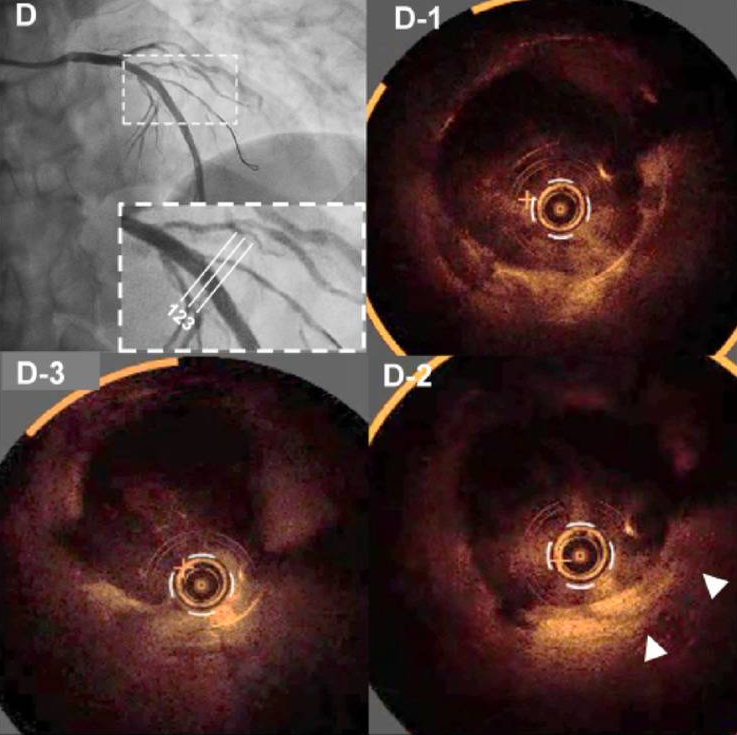

最后,对LAD病变处应用3.5×30mm紫杉醇涂层球囊(SeQuent Please Neo)扩张,并以对吻球囊技术同时扩张了LAD和对角支,以保证分叉部位的几何形态(图C)。最终OCT显示病变充分扩张,突起的斑块组织被压缩(图D、D1-3)。

D、D1-3 最终OCT图像显示病变充分扩张,突起的斑块组织被压缩